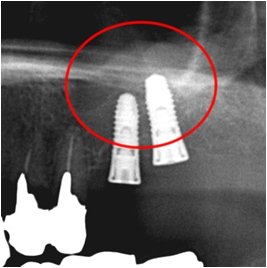

インプラント埋入後のレントゲン写真